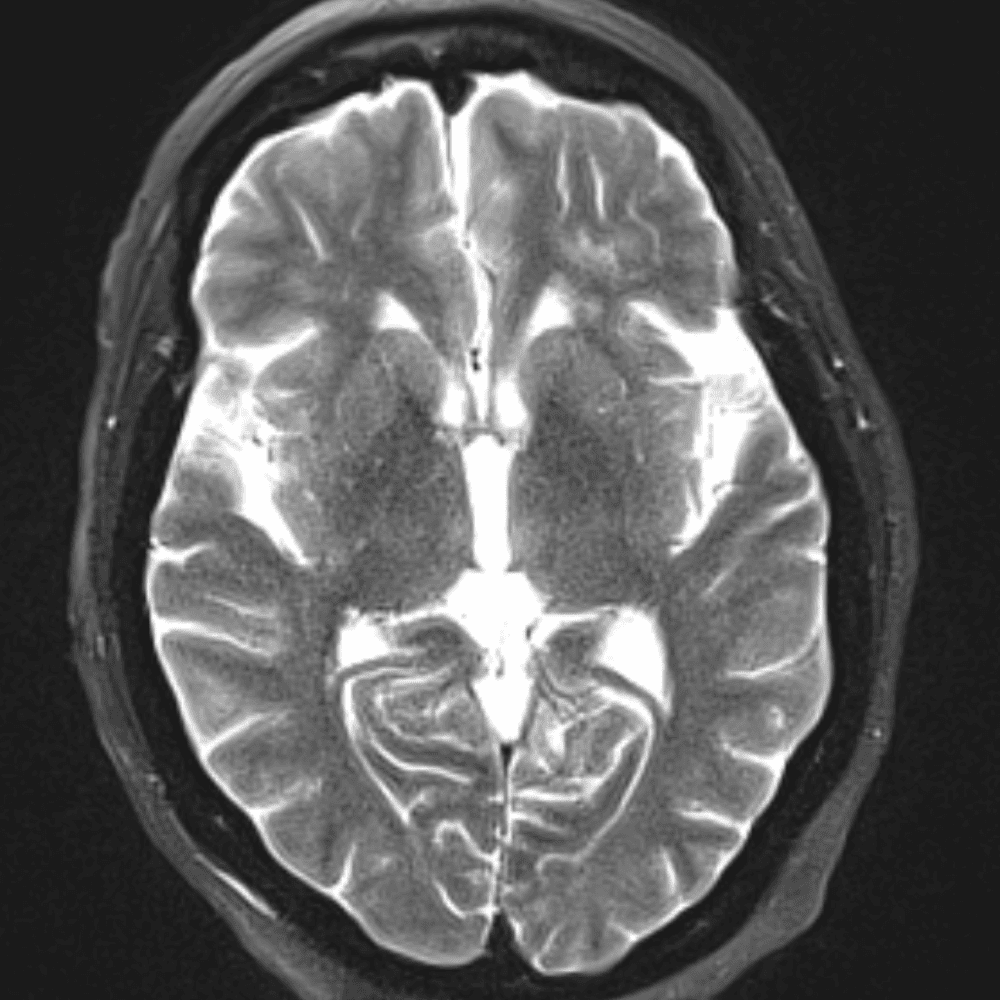

๋‹น์ง ์‹œ ํ”ํžˆ ๋ณผ ์ˆ˜ ์žˆ๋Š” ์‚ฌ๋ก€์˜ ์ „ํ˜•์ ์ธ ์˜ˆ๋ฅผ ํฌํ•จํ•ฉ๋‹ˆ๋‹ค.

39 ์‚ฌ๋ก€

์—ฐ์Šต

๋ฏธ๋ฌ˜ํ•˜๊ฑฐ๋‚˜ ์–ด๋ ค์šด ์‚ฌ๋ก€์™€ ์ผ๋ถ€ ์ •์ƒ ์‚ฌ๋ก€๋ฅผ ํฌํ•จํ•˜์—ฌ ๋‹น์ง์„ ์‹œ๋ฎฌ๋ ˆ์ด์…˜ํ•ฉ๋‹ˆ๋‹ค.

50 ์‚ฌ๋ก€